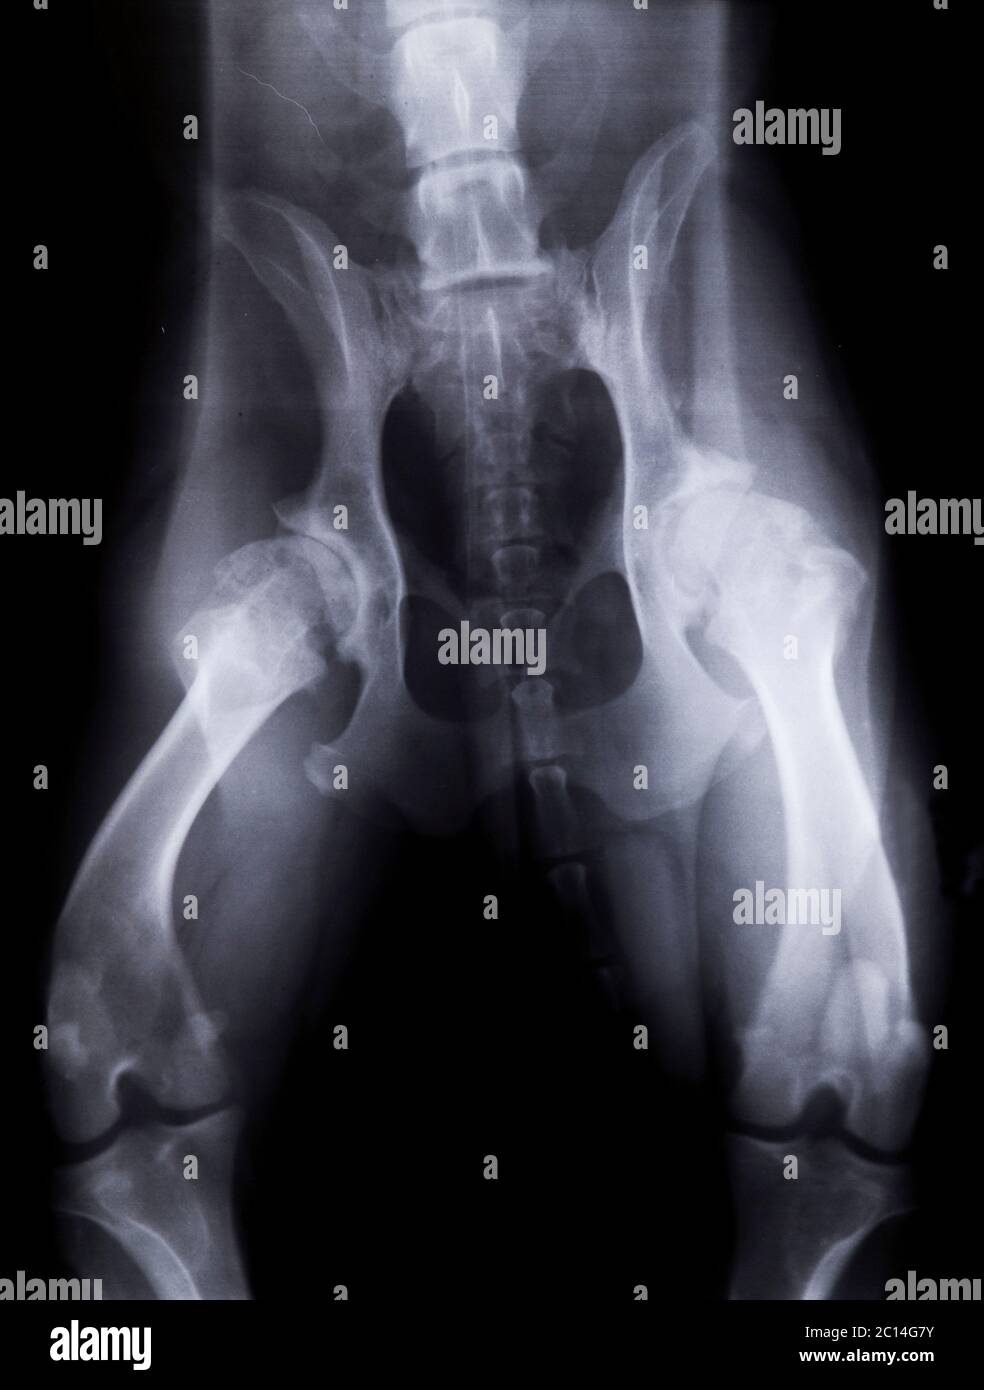

Xray of a dog with severe hip dysplasia Stock Photo Alamy Canine Hip Xray Chd is diagnosed by a combination of two. Femoral head subluxation or luxation. 8,9 radiographs are recommended for dogs aged 5 to 10 months with hip joint laxity and clinical signs of hip dysplasia (e.g., lameness, bunny hopping, gait abnormalities, pain on manipulation). canine hip dysplasia (cho) is a highly prevalent multifactorial disorder. Although the etiology is not completely. Canine Hip Xray.

Dog X Ray Showing Canine Bilateral Hip Dysplasia. Ventral View Stock Canine Hip Xray The breed specific statistics and a more detailed explanation can be viewed at www.bva.co.uk/chs. 8,9 radiographs are recommended for dogs aged 5 to 10 months with hip joint laxity and clinical signs of hip dysplasia (e.g., lameness, bunny hopping, gait abnormalities, pain on manipulation). Although the etiology is not completely understood,. Femoral head subluxation or luxation. the radiological findings. Canine Hip Xray.